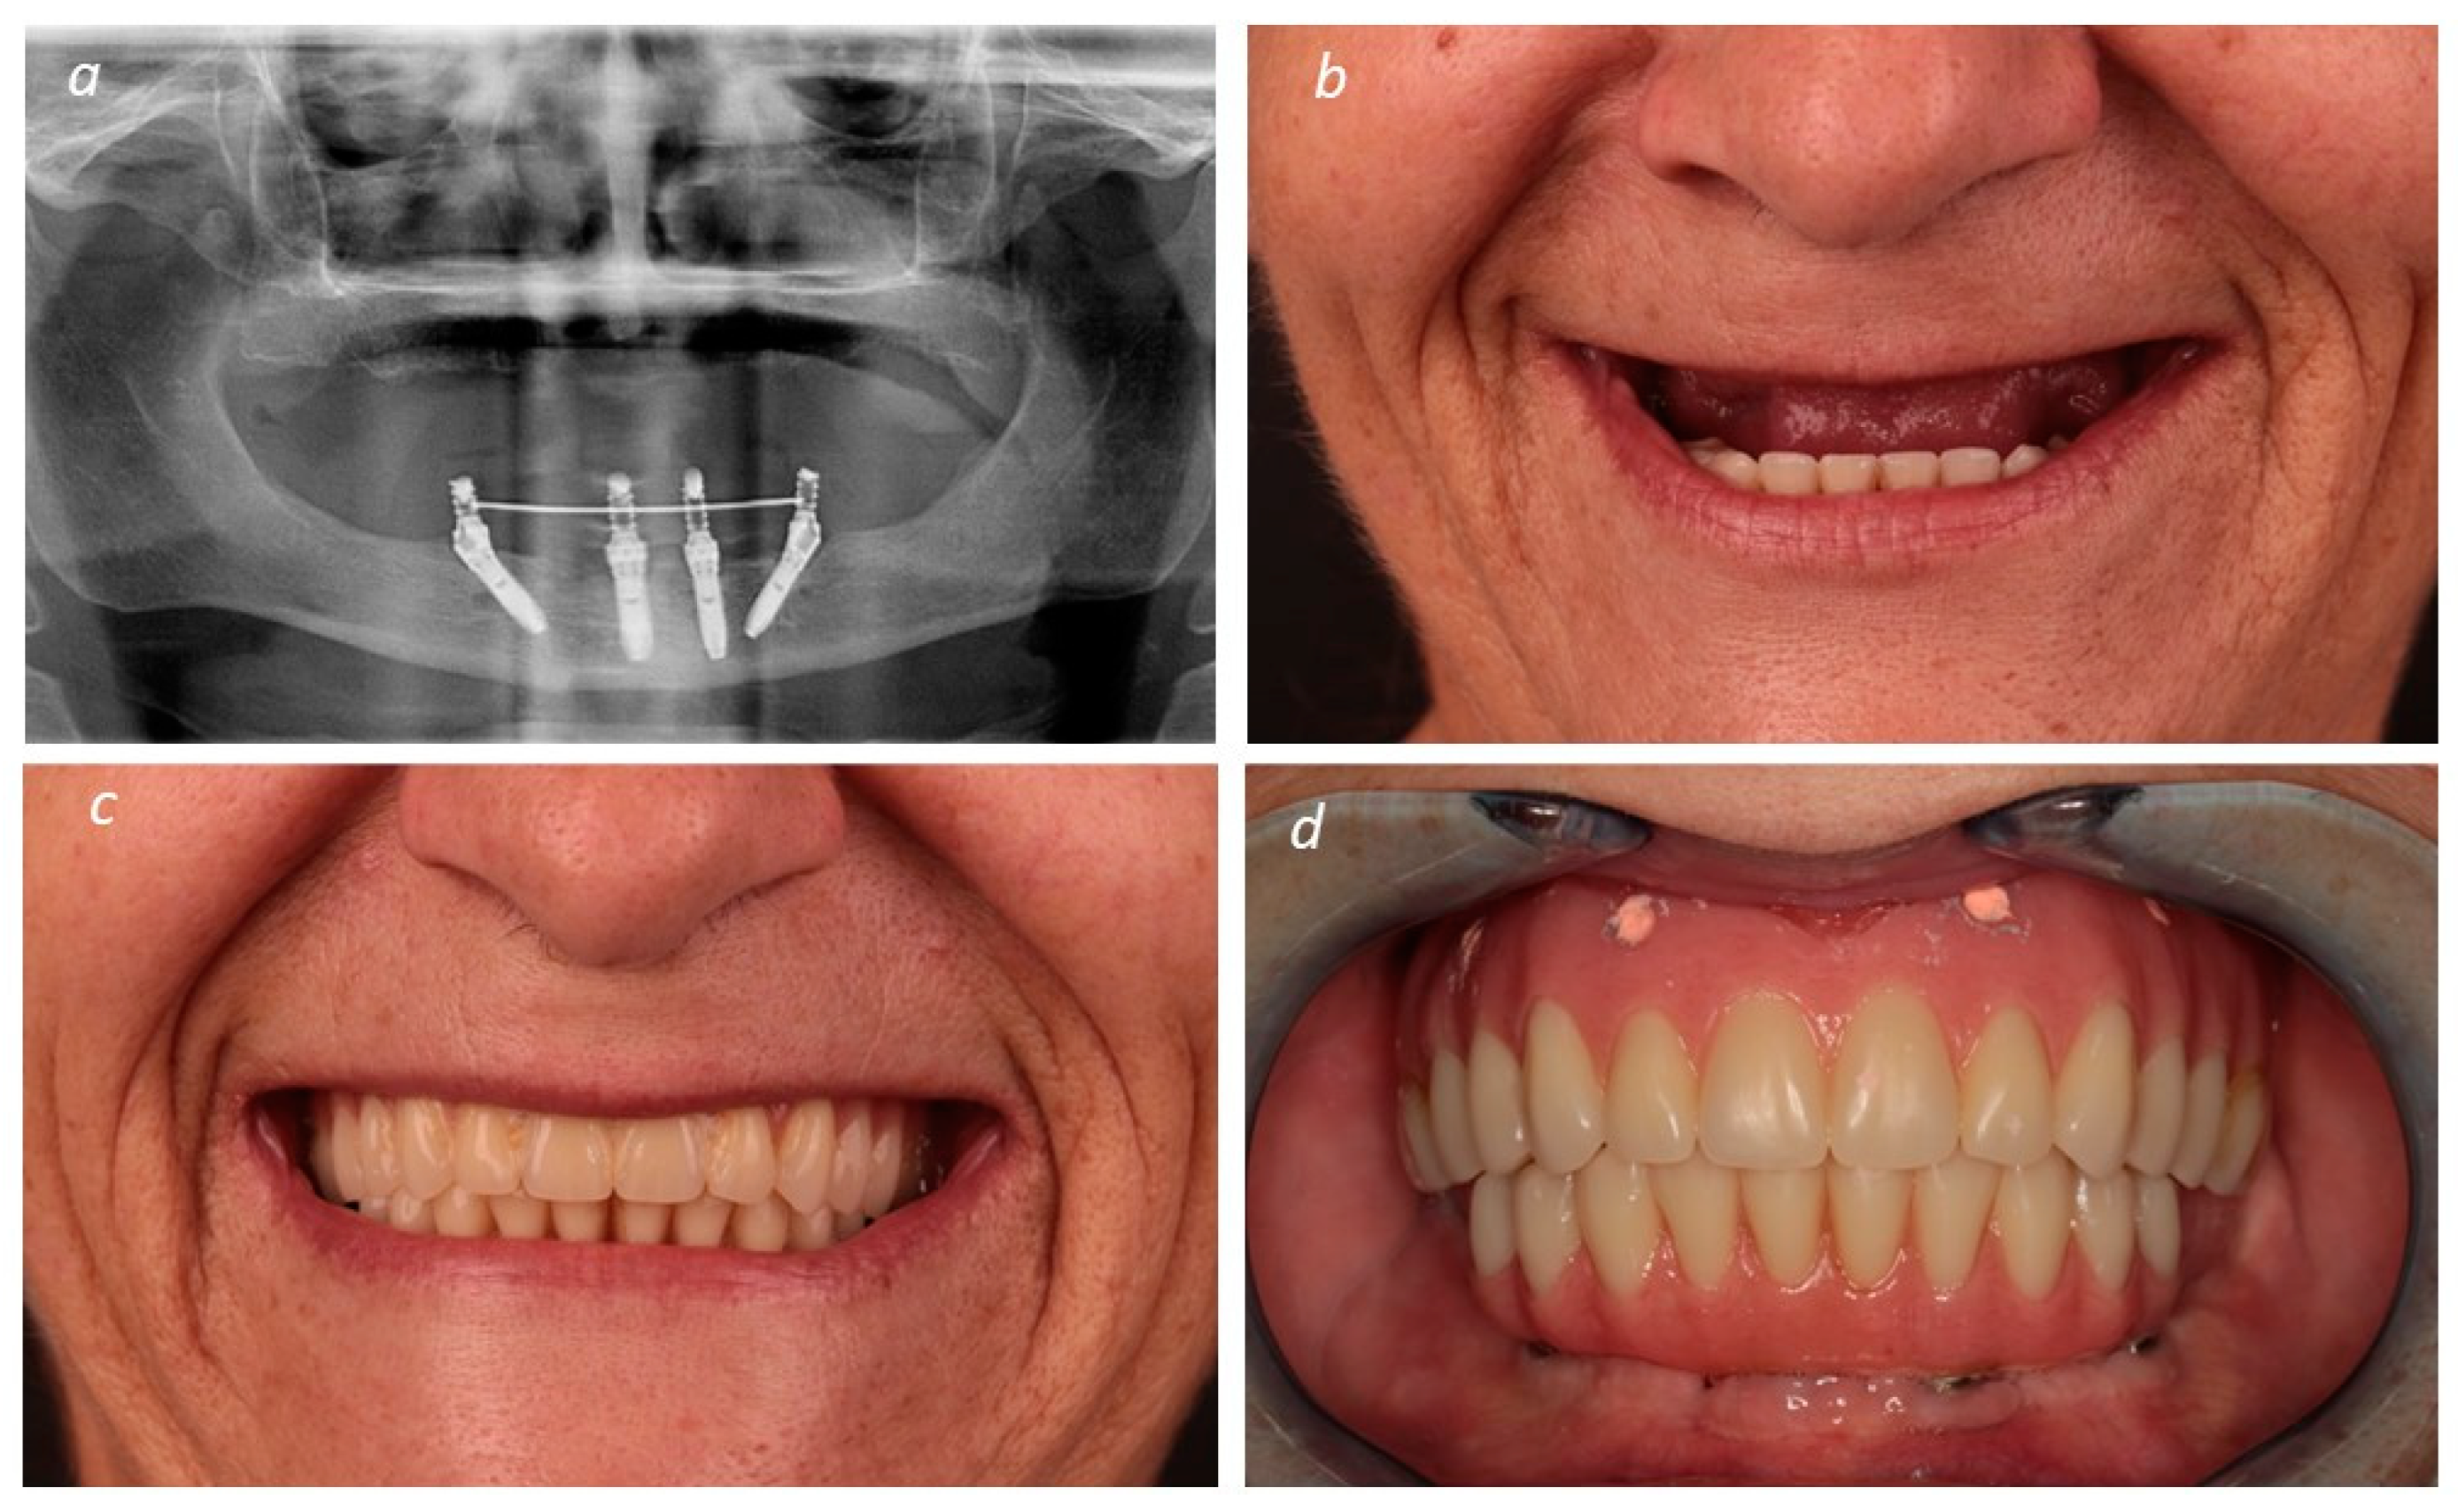

2. Materials and Methods

Description of the Technique

3. Results